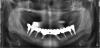

фима Опубликовано 20 октября, 2011 Поделиться Опубликовано 20 октября, 2011 Блэйд низ справа забивал в 88 году , Ну и практически за это время не видел. Теперь как обычно- хочу все и сразу - как все.По ОПГ интерпретировать патологию сложно , но готовят фото удаленных зубов- там все ясно.Выложу. Низ- убрали все , с блэйдом покувыркались , поставили все , и немедленная нагрузка.На месте блэйда сильно неудобно было , поэтому заглушил , Остался запаской. Ссылка на комментарий

фима Опубликовано 20 октября, 2011 Поделиться Опубликовано 20 октября, 2011 Через 2 -3 недели верх - выбросили все и поставил , где мог. Опять немедленная нагрузка.ОПГ сделана во время , пока делали временный.Слева планировал доставить после заживления. Ссылка на комментарий

фима Опубликовано 20 октября, 2011 Поделиться Опубликовано 20 октября, 2011 Через 7 мес постоянное протезирование. Итог- ушел один имплант неудача ,кажется вверху справа то ли 2 , то ли 3. , когда снимали временную , конструкцию, но там и так по состоянию слизистой было видно , что там проблемы . . От доставки имплантов слева после удачной времянки отказалась - для улыбания мол , хватит , пойду наслаждаться жизнью. Чувствую , опять надолго. Ссылка на комментарий

фима Опубликовано 25 октября, 2011 Поделиться Опубликовано 25 октября, 2011 Насколько я понял в верху съемник и его не трогали, в этом и вся радость.Да вот получилось и со своими зубами вверху. Отходила с двумя времянками . ОПГ показывал выше , добавляю фото. По порядку не грузится , но, я думаю, разберетесь.Нет фото верхней времянки - мне жаль. Ссылка на комментарий

pit Опубликовано 25 октября, 2011 Поделиться Опубликовано 25 октября, 2011 Спасибо за фотки, временные винты установлены параллельнее, чем постоянныеА фотографий окончательной работы у Вас нет? Ссылка на комментарий